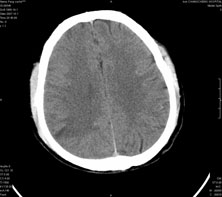

男,41岁,间断抽搐1小时,失神5分钟,bp130/90mmhg。低密度区ct值约16hu。

脑实质见多发散在的钙化点,左顶叶见一囊变灶,多考虑脑囊虫。

脑实质见多发散在的钙化点,右颞、顶叶见囊性灶,考虑脑囊虫。

多发的囊泡(多发囊型)+多发的钙化(慢性钙化型)=混合型

顶叶最大的囊直径2.2cm,如果考虑囊虫的话,囊是不是有点儿太大了?